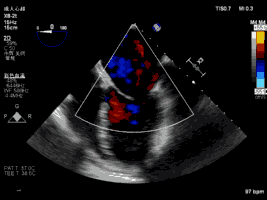

夾合術(shù)前:彩色多普勒示重度二尖瓣反流